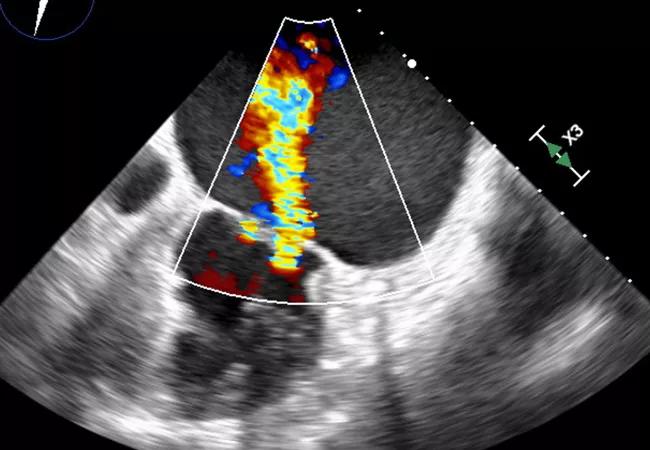

“Typically, AFMR requires transesophageal echo to ascertain,” Dr. Harb explains (see Figure). “However, the diagnosis of MR should start with a transthoracic echo and proceed to transesophageal echo if an unusual form of MR is suspected, in which case transesophageal echo can help elucidate the features of AFMR.”

Figure. Top transesophageal echocardiogram (TEE) shows a markedly enlarged left atrial (LA) cavity with no mitral valve (MV) leaflet pathology and a normal left ventricle (LV). Bottom TEE shows severe atrial functional (or secondary) mitral regurgitation (AFMR).